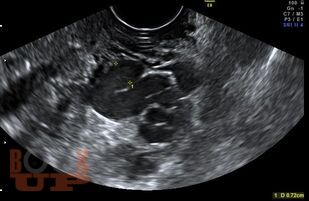

В учебном пособии изложены современные принципы ультразвуковой диагностики вен таза. Представлена анатомия вен малого таза, этиопатогенез, классификация этого заболевания. Приводятся рекомендации о методике ультразвукового исследования вен таза. Учебное пособие предназначено для врачей, обучающихся по программам дополнительного профессионального образования по специальностям «Ультразвуковая диагностика», «Сердечно-сосудистая хирургия».